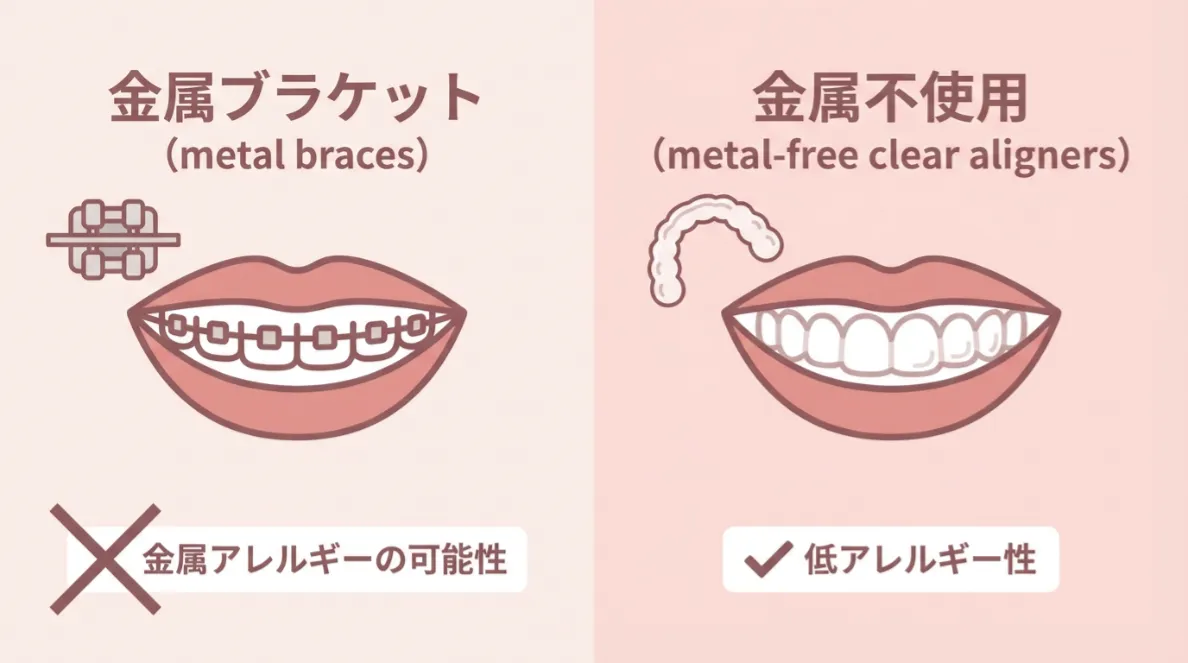

金属アレルギーの心配がない

マウスピースは金属を使わないため、金属アレルギーの方でも利用しやすい治療法です。金属ブラケットに抵抗がある方にも選ばれています。